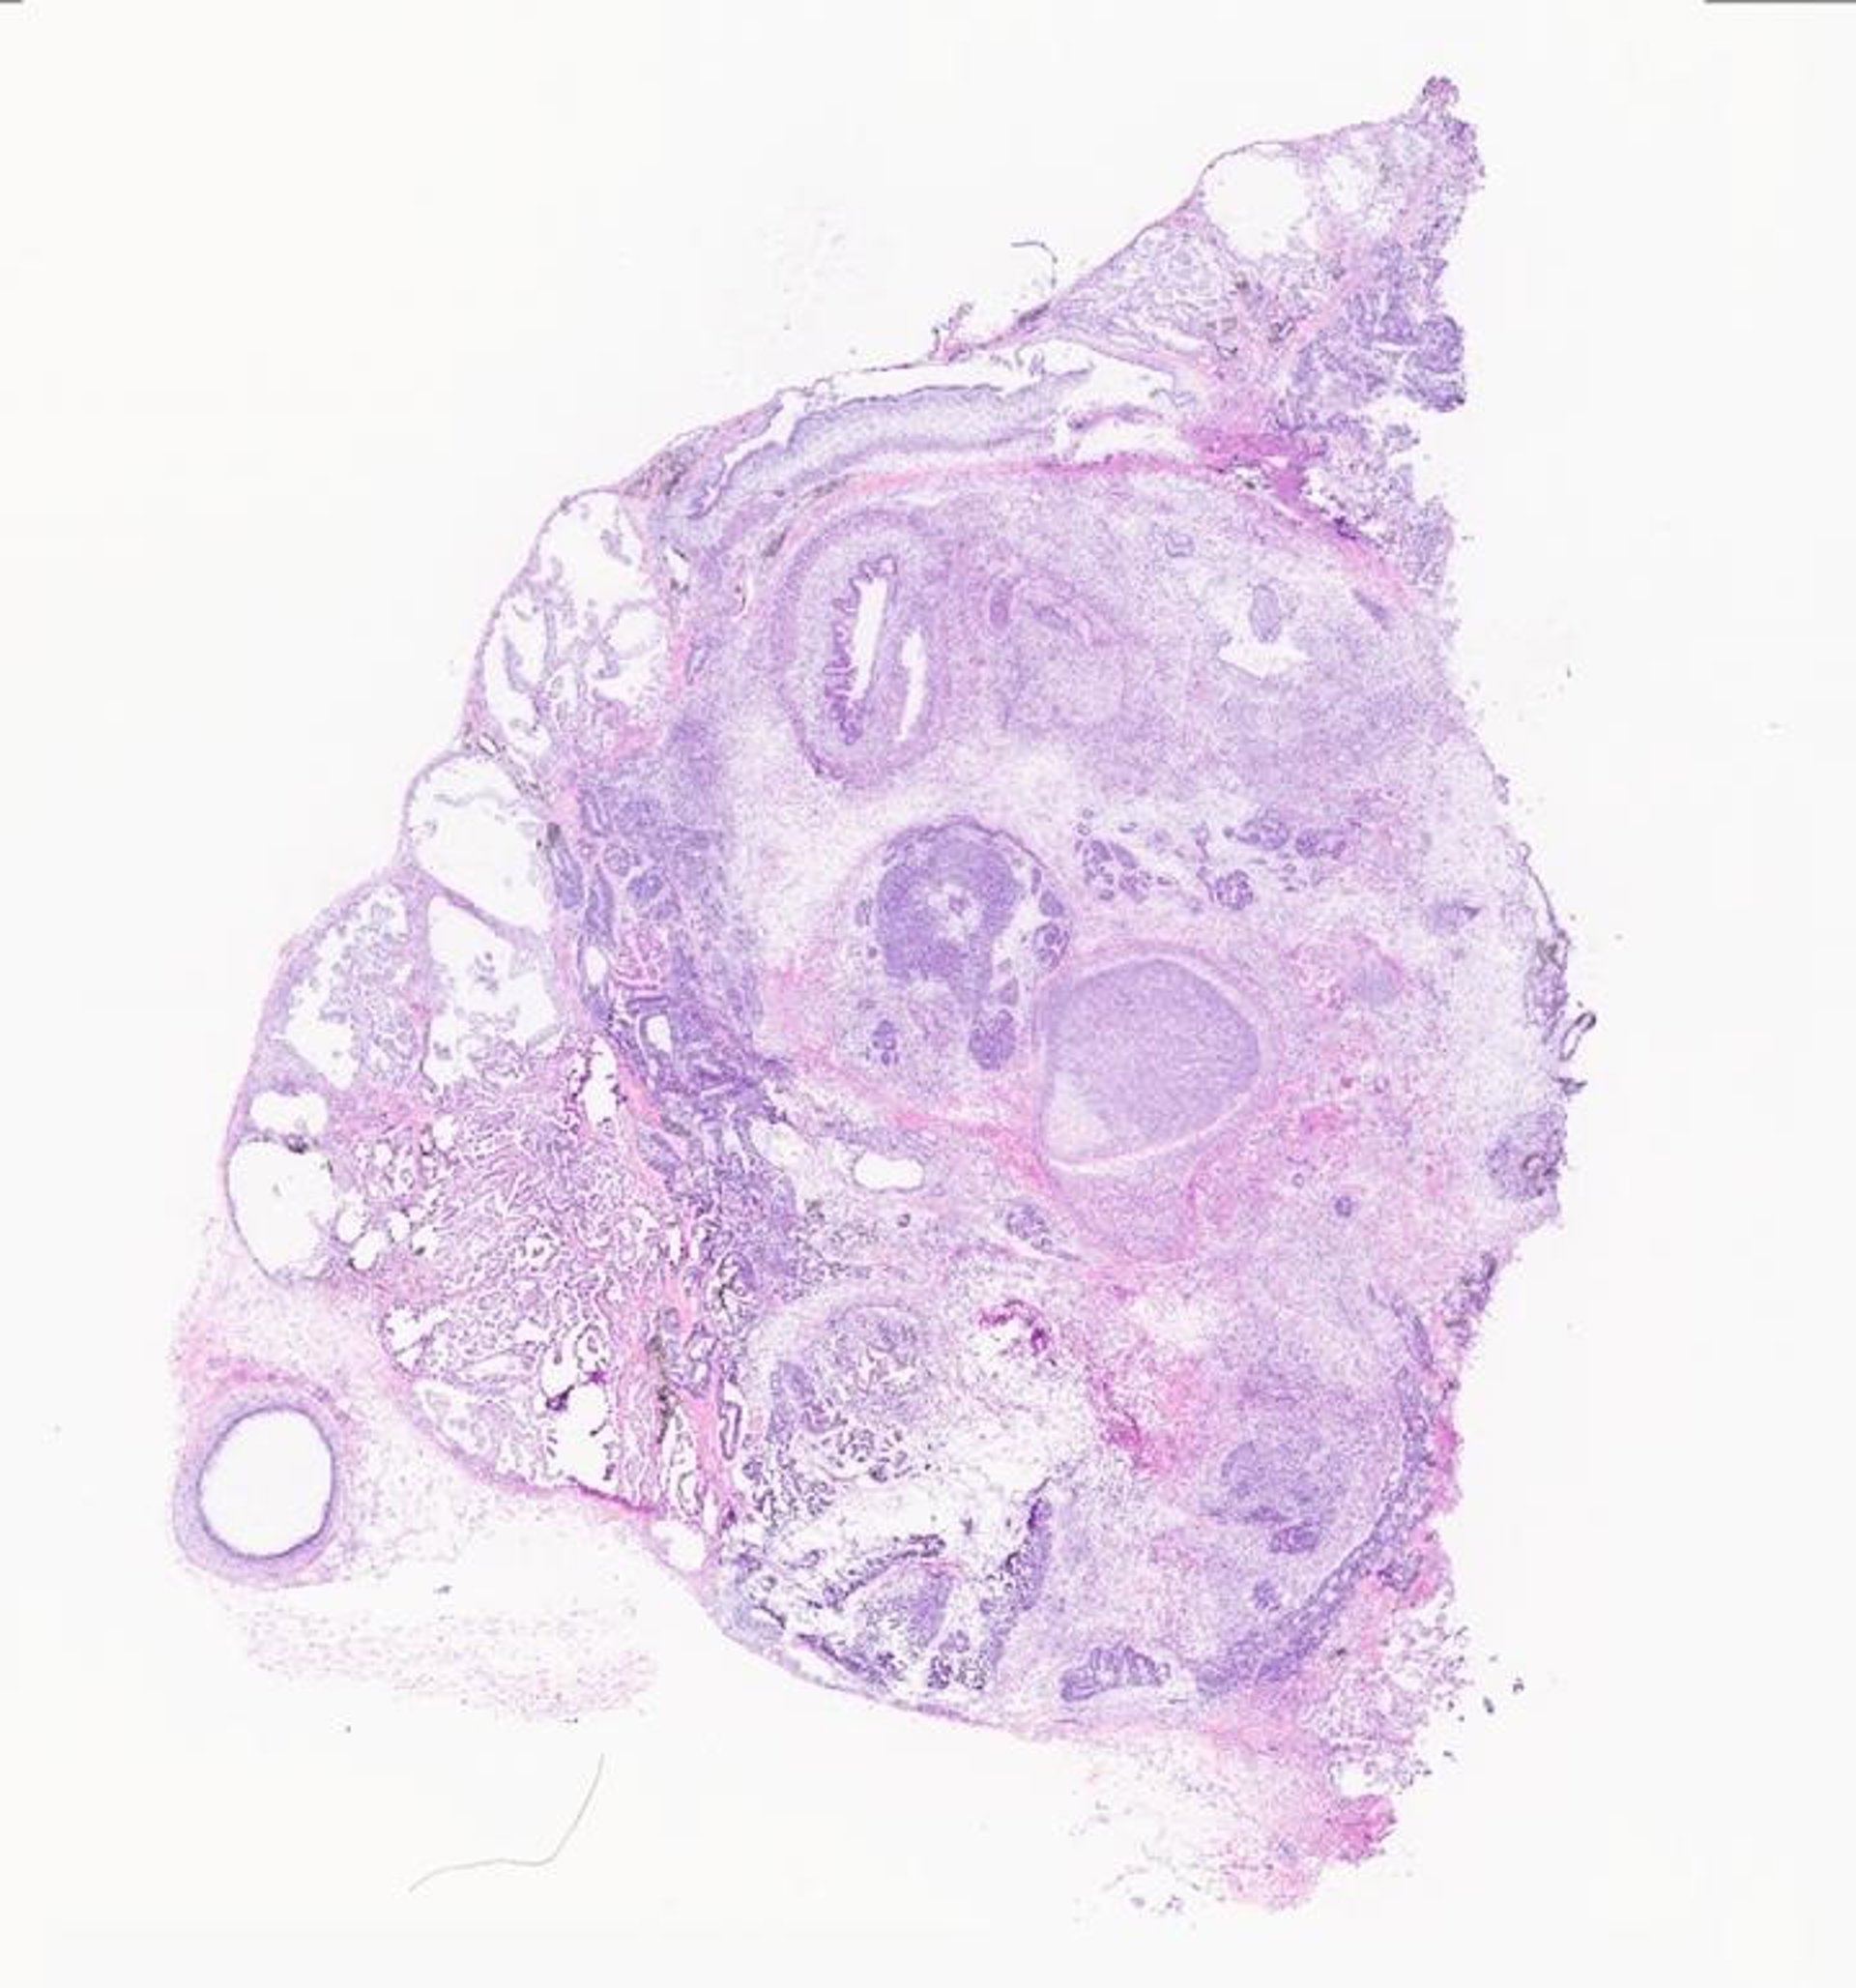

Histología de un teratoma.

Histología de un teratoma. - DANIELLA MCDONALD

Los teratomas, que significan "tumores monstruosos" en griego, son tumores formados por diferentes tejidos como huesos, cerebro, cabello y músculos. Se forman cuando una masa de células madre se diferencia incontrolablemente, formando todo tipo de tejidos que se encuentran en el cuerpo. Los teratomas generalmente se consideran un subproducto no deseado de la investigación con células madre, pero los investigadores de UC San Diego encontraron la oportunidad de estudiarlos como modelo para el desarrollo humano.

El equipo utilizó teratomas cultivados a partir de células madre humanas inyectadas bajo la piel de ratones inmunodeficientes. Analizaron los teratomas con una técnica llamada secuenciación de ARN unicelular, que perfila la expresión génica de las células de teratoma individuales. Pudieron mapear 20 tipos de células, o "linajes humanos" (cerebro, intestino, músculo, piel, etc.) que estaban presentes de manera constante en todos los teratomas que analizaron.